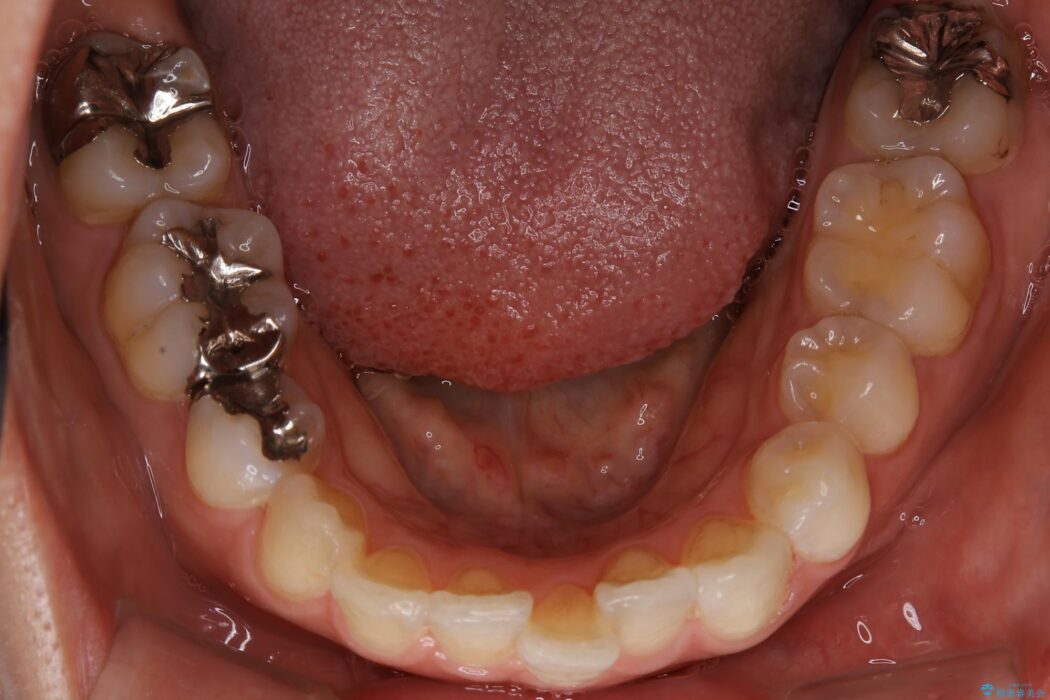

【20代女性】矯正治療後の後戻り

- 患者様:20代女性

- 治療期間:1年

- 矯正装置:審美装置

- 概算治療費:66万円

抜歯矯正後の後戻りについてご相談にいらした患者様です、